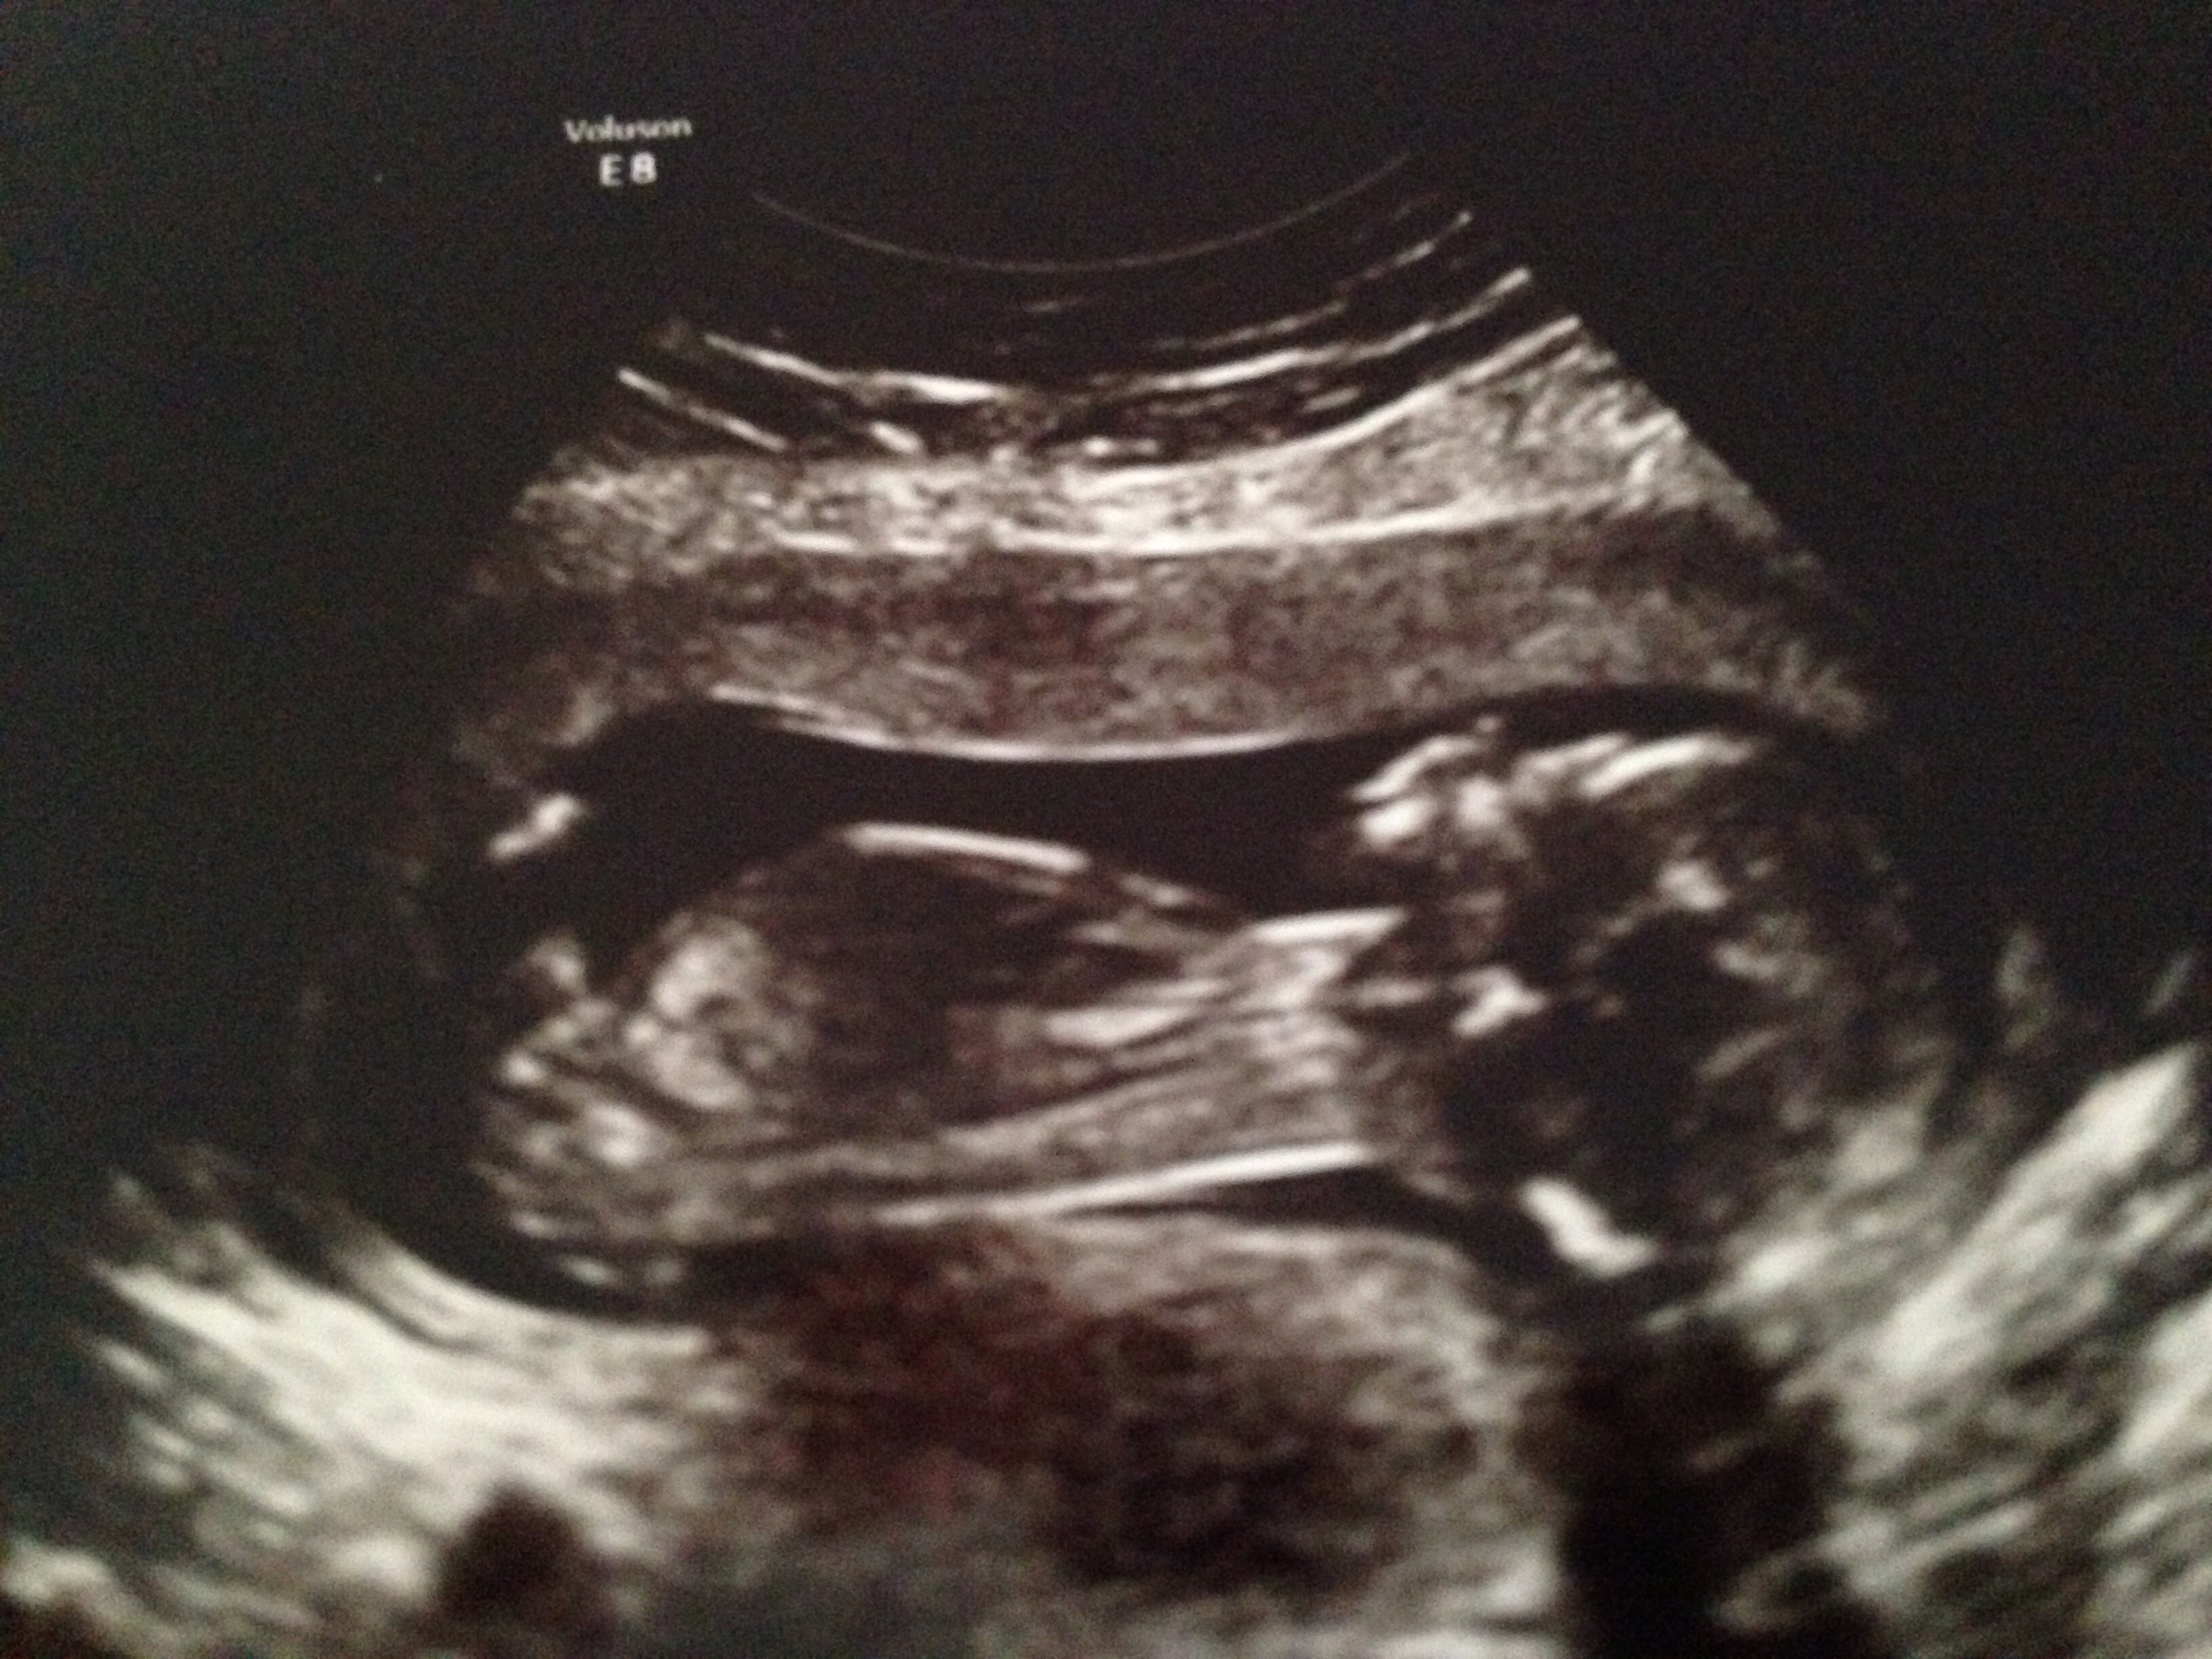

Had our anatomy scan today. Everything looked good except the little stinker was too balled up to see the heart good so I get to go back in six weeks for another look.